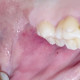

Alo dokter, seorang pasien dengan keluhan terdapat bintik hitam seperti tahi lalat di dalam rongga mulut, tidak ada rasa sakit sama sekali, mohon bantuan dan tindakan yang harus dilakukan seperti apa. Terima kasih

Berikut saya lampirkan fotonya

drg. Erni Marlina, Ph.D., Sp, PM.,SubSp. Inf(K)

Alodok, mungkin perlu dianamnesa lebih lanjut dok, apa penyebabnya. Kl saya liat dari fotonya seperti trauma krn gigitan yg tidak disadari pasien dok. Bila tidak ada keluhan biarkan saja dok, akan hilang sendiri, tetapi bila ada keluhan bisa diberikan gel hyaluronate acid seperti aloclair dok, untuk konsultasi dan pengobatan lebih lanjut silahkan konsultasi ke drg spesialis penyakit mulut. Terimakasih